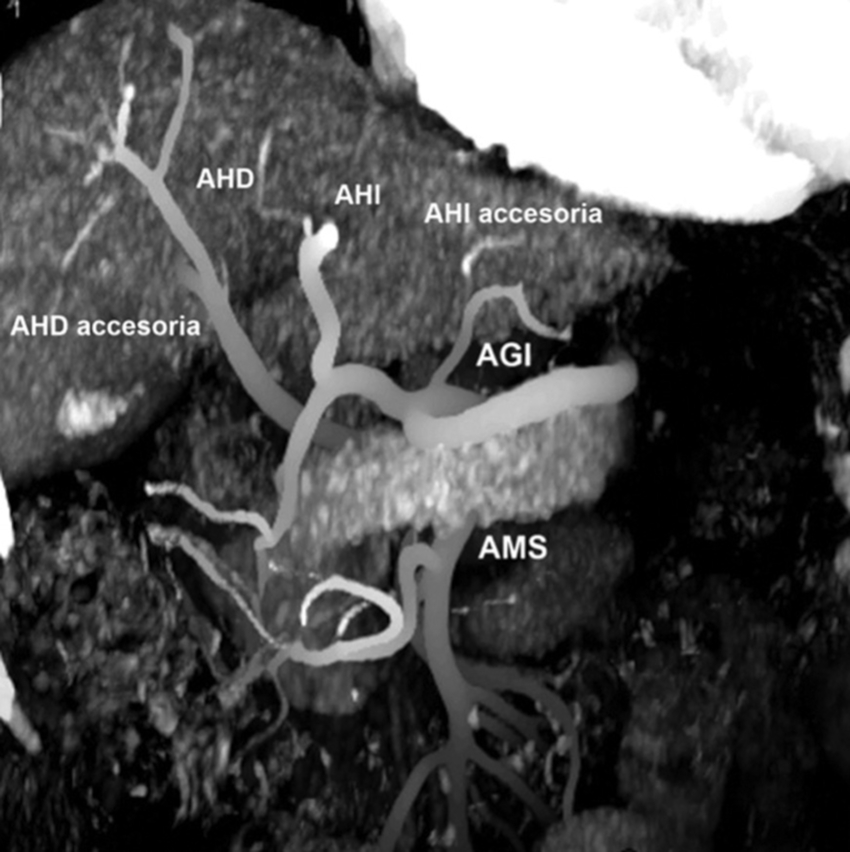

Tipo 3: AHD aberrante con origen en la AMS. AHI con origen en la AHC (Figs. 6 y 7).

Tipo 6: AHD y AHI con origen en la AHC. AHD accesoria desde la AMS (Figs. 11 y 12).

Tipo 9: la AHC emerge de la AMS (Fig. 17).

Además, se observaron variantes fuera de la clasificación de Michels en 6 casos (2.2%): ausencia del tronco celíaco en 3 casos, tronco celíaco mesentérico en 2 casos (Fig. 18), y arterias hepáticas aberrantes derecha e izquierda originarias de AMS en 1 caso. Asimismo, en 3 casos de la variante tipo 1 de Michels se observaron los hallazgos asociados del arco de Bühler (Fig. 19).